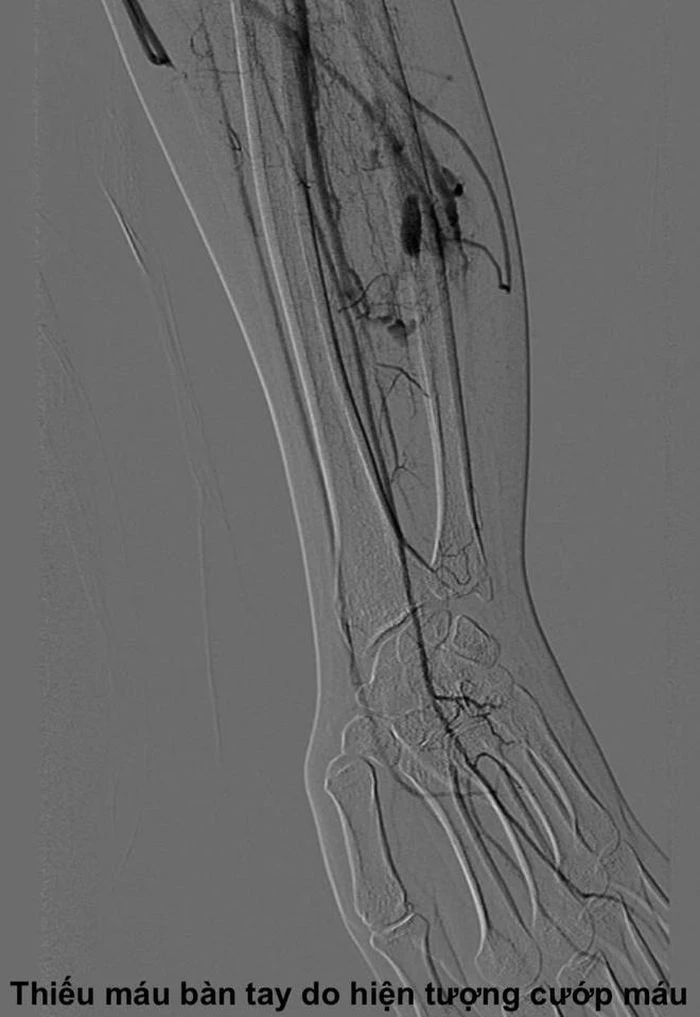

TS. Cương giải thích, dòng máu tốc độ cao đi tắt qua ổ dị dạng này sẽ không kịp cung cấp oxy và dưỡng chất cho vùng mô ở phía hạ lưu. Điều này dẫn đến hiện tượng “ăn cắp máu” (steal phenomenon), tức là ổ dị dạng hút máu từ các mạch máu bình thường lân cận, khiến các ngón tay hoặc chi bị thiếu máu nuôi mạn tính. Đây chính là nguyên nhân gây ra các triệu chứng đau, tê, sưng, nóng , hoặc thậm chí biến dạng chi của bệnh nhân Q.

Sau khi hội chẩn kỹ lưỡng, các bác sĩ quyết định không phẫu thuật mở truyền thống mà chỉ định cho bệnh nhân L.Q. thực hiện phương pháp can thiệp nút mạch qua da – một kỹ thuật điện quang can thiệp hiện đại, ít xâm lấn.

Dưới sự hướng dẫn của máy chụp mạch kỹ thuật số (DSA), bác sĩ sử dụng một cây kim rất nhỏ chọc trực tiếp qua da, đi chính xác vào ổ dị dạng nằm sâu trong cơ cẳng tay. Sau đó, cồn tuyệt đối (absolute ethanol) được bơm vào qua kim để làm xơ hóa và bịt kín hoàn toàn các mạch máu bất thường.